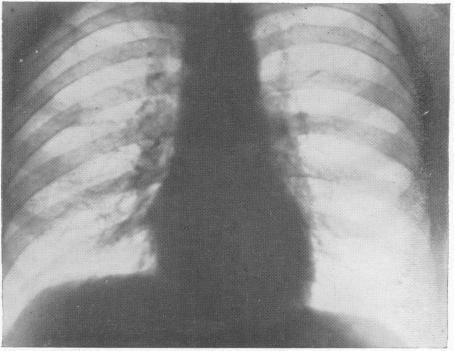

THE EFFECT OF OBSTRUCTED RESPIRATION ON HEART AND LUNGS: ITS CLINICAL IMPORTANCE IN RADIOGRAPHY.

Br Med J. 1929 Mar 9;1(3557):439-438.2. doi: 10.1136/bmj.1.3557.439.